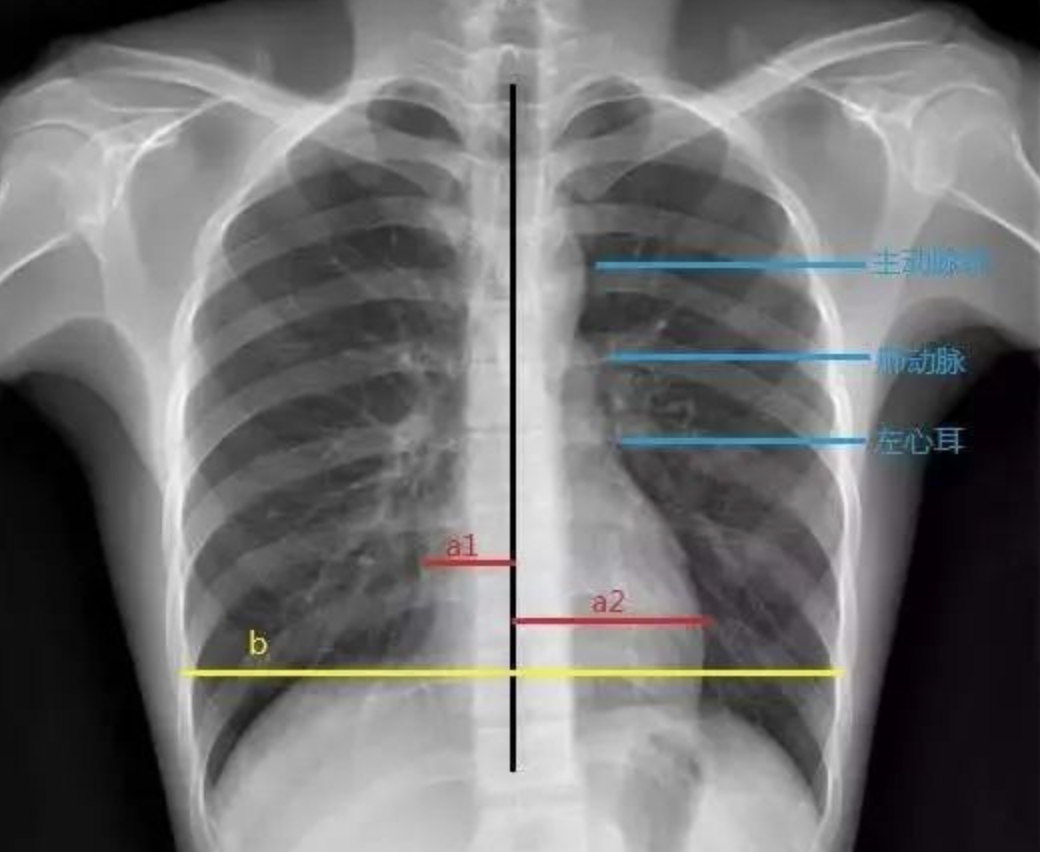

要么是心脏本身增大(心包积液—烧瓶心)要么是心包里面灌了水普大型

其典型胸片表现为心影增大,即所谓的烧瓶状心脏.